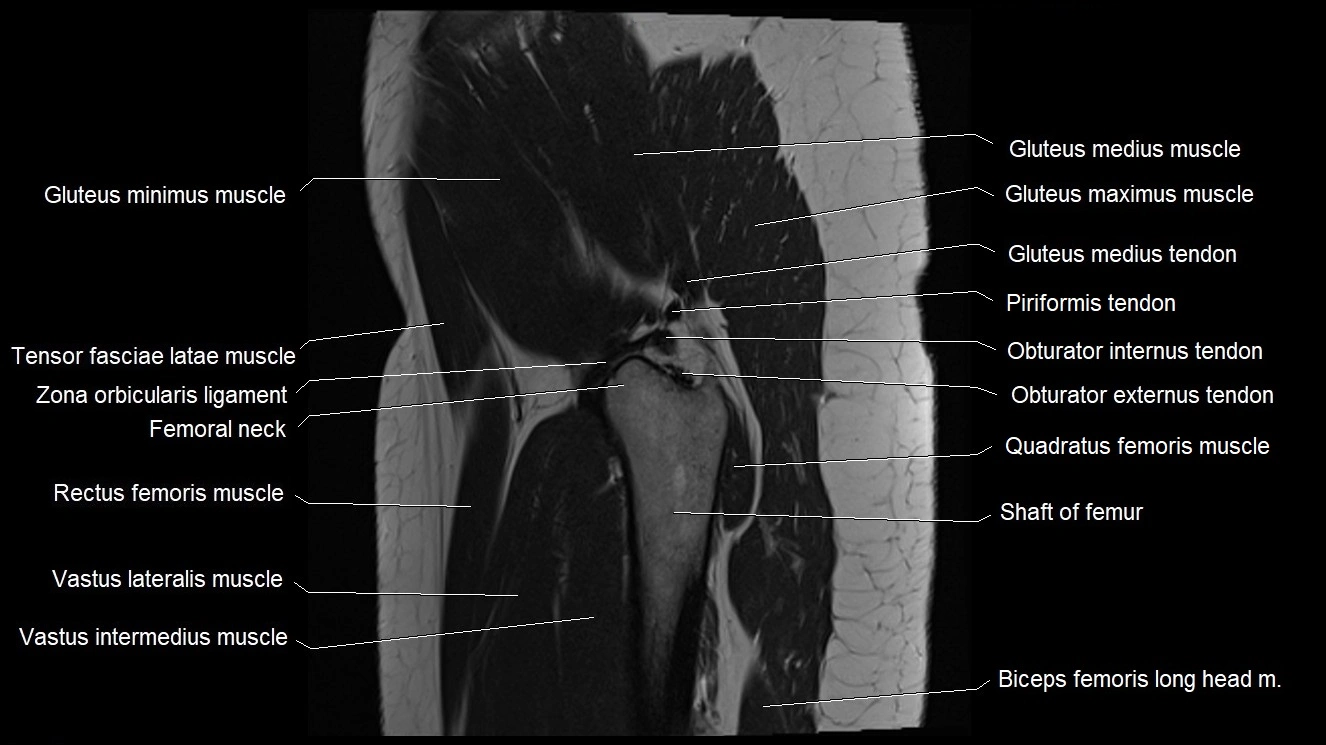

- Gluteus maximus muscle

- Gluteus medius muscle

- Gluteus medius tendon

- Gluteus minimus muscle

- Gluteus minimus tendon

- Greater trochanter

- Head of femur

- Hip joint

- Neck of femur

- Obturator externus tendon

- Obturator internus tendon

- Quadratus femoris muscle

- Tensor fasciae latae muscle

- Vastus intermedius muscle

- Vastus lateralis muscle

- Zona orbicularis ligament